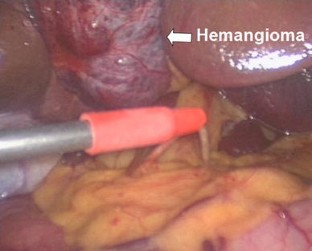

Modified laparoscopic hepatectomy for hepatic hemangioma

Laparoscopic hepatectomy (LH) using many different surgical techniques has become increasingly popular for the management of hepatic tumors. The performance of surgical procedures involving the least possible impairment is expected increasingly more often by both surgeons and patients. We herein describe a clinical cohort of ten patients with hepatic cavernous hemangioma (HCH) who underwent modified LH (MLH) with a new technique. We herein present the advantages of the low level of impairment during performance of this modified procedure and compare the outcomes of MLH with those of traditional LH (TLH) for HCH.

Fig. 1